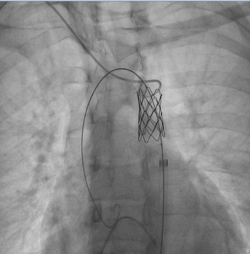

Михаил Ташник, интервенционный кардиолог: «Операция проходила в нашей лаборатории ангиографии катетеризации сердца, длилась полтора часа под общей анестезией для удобства пациента и врачей. Через небольшое отверстие на уровне артерии ноги была введена специальная трубка до уровня сужения, где в месте коарктации был имплантирован стент. Стент представляет собой водонепроницаемую медицинскую сетку, которая не только снижает степень сужения, но и сводит к минимуму любой риск возникновения разрыва аорты. Результаты и успешность случая пациентки стали возможны благодаря совместной работе врачей Medpark и коллег из Турции».

Интраоперационные риски при таких вмешательствах составляют менее 5%, а выздоровление пациента занимает менее 24 часов.

Операция была проведена в сотрудничестве с коллегами из Турции под руководством профессора Айдына, всемирно известного врача, которому ассистировали интервенционные кардиологи Ераслан Хакан и Михаил Ташник. Комфортабильность и успех вмешательства стали возможны также благодаря эффективному сотрудничеству с отделением интенсивной терапии и профессионализму врача-анестезиолога Ивана Ешану в области общей анестезии пациентов с сердечно-сосудистыми патологиями. Все перечисленные факторы обеспечили максимальную безопасность хирургического вмешательства как для врачей, так и для пациента.